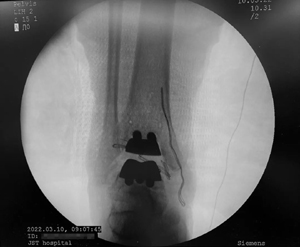

3D打印定制化全踝关节置换术后X线11111111111111111定制化3D截骨导板111111111111

昨日,北京积水潭医院足踝外科武勇主任团队率先完成国内第一例3D打印定制化全踝关节置换。手术整体耗时约2小时,比传统的全踝关节置换术足足减少了1个小时。手术后假体位置力线良好,关节张力平衡,活动改善明显。